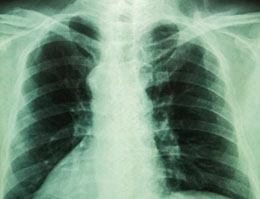

You should consult your doctor and find out the exact cause of chest pain and breathing difficulty. This would help design proper treatment. CT scan, chest X-ray, ECG, etc. help detect the underlying cause.